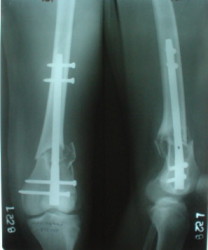

1

2

The mobilisation of knee is started immediately from the second day. Weight bearing is permitted as in any other interlocked nailing. That is, Toe touch to start with and within four days, partial to in another two weeks, full weight bearing. Of course that is assuming that the correct size nail has been used. Up to 70 kg body weight, 11no will be good enough and 12mm if more.Usually at the 1st followup, at 6 weeks time, they have full flexion..I

Enclosing a recent intraop picture